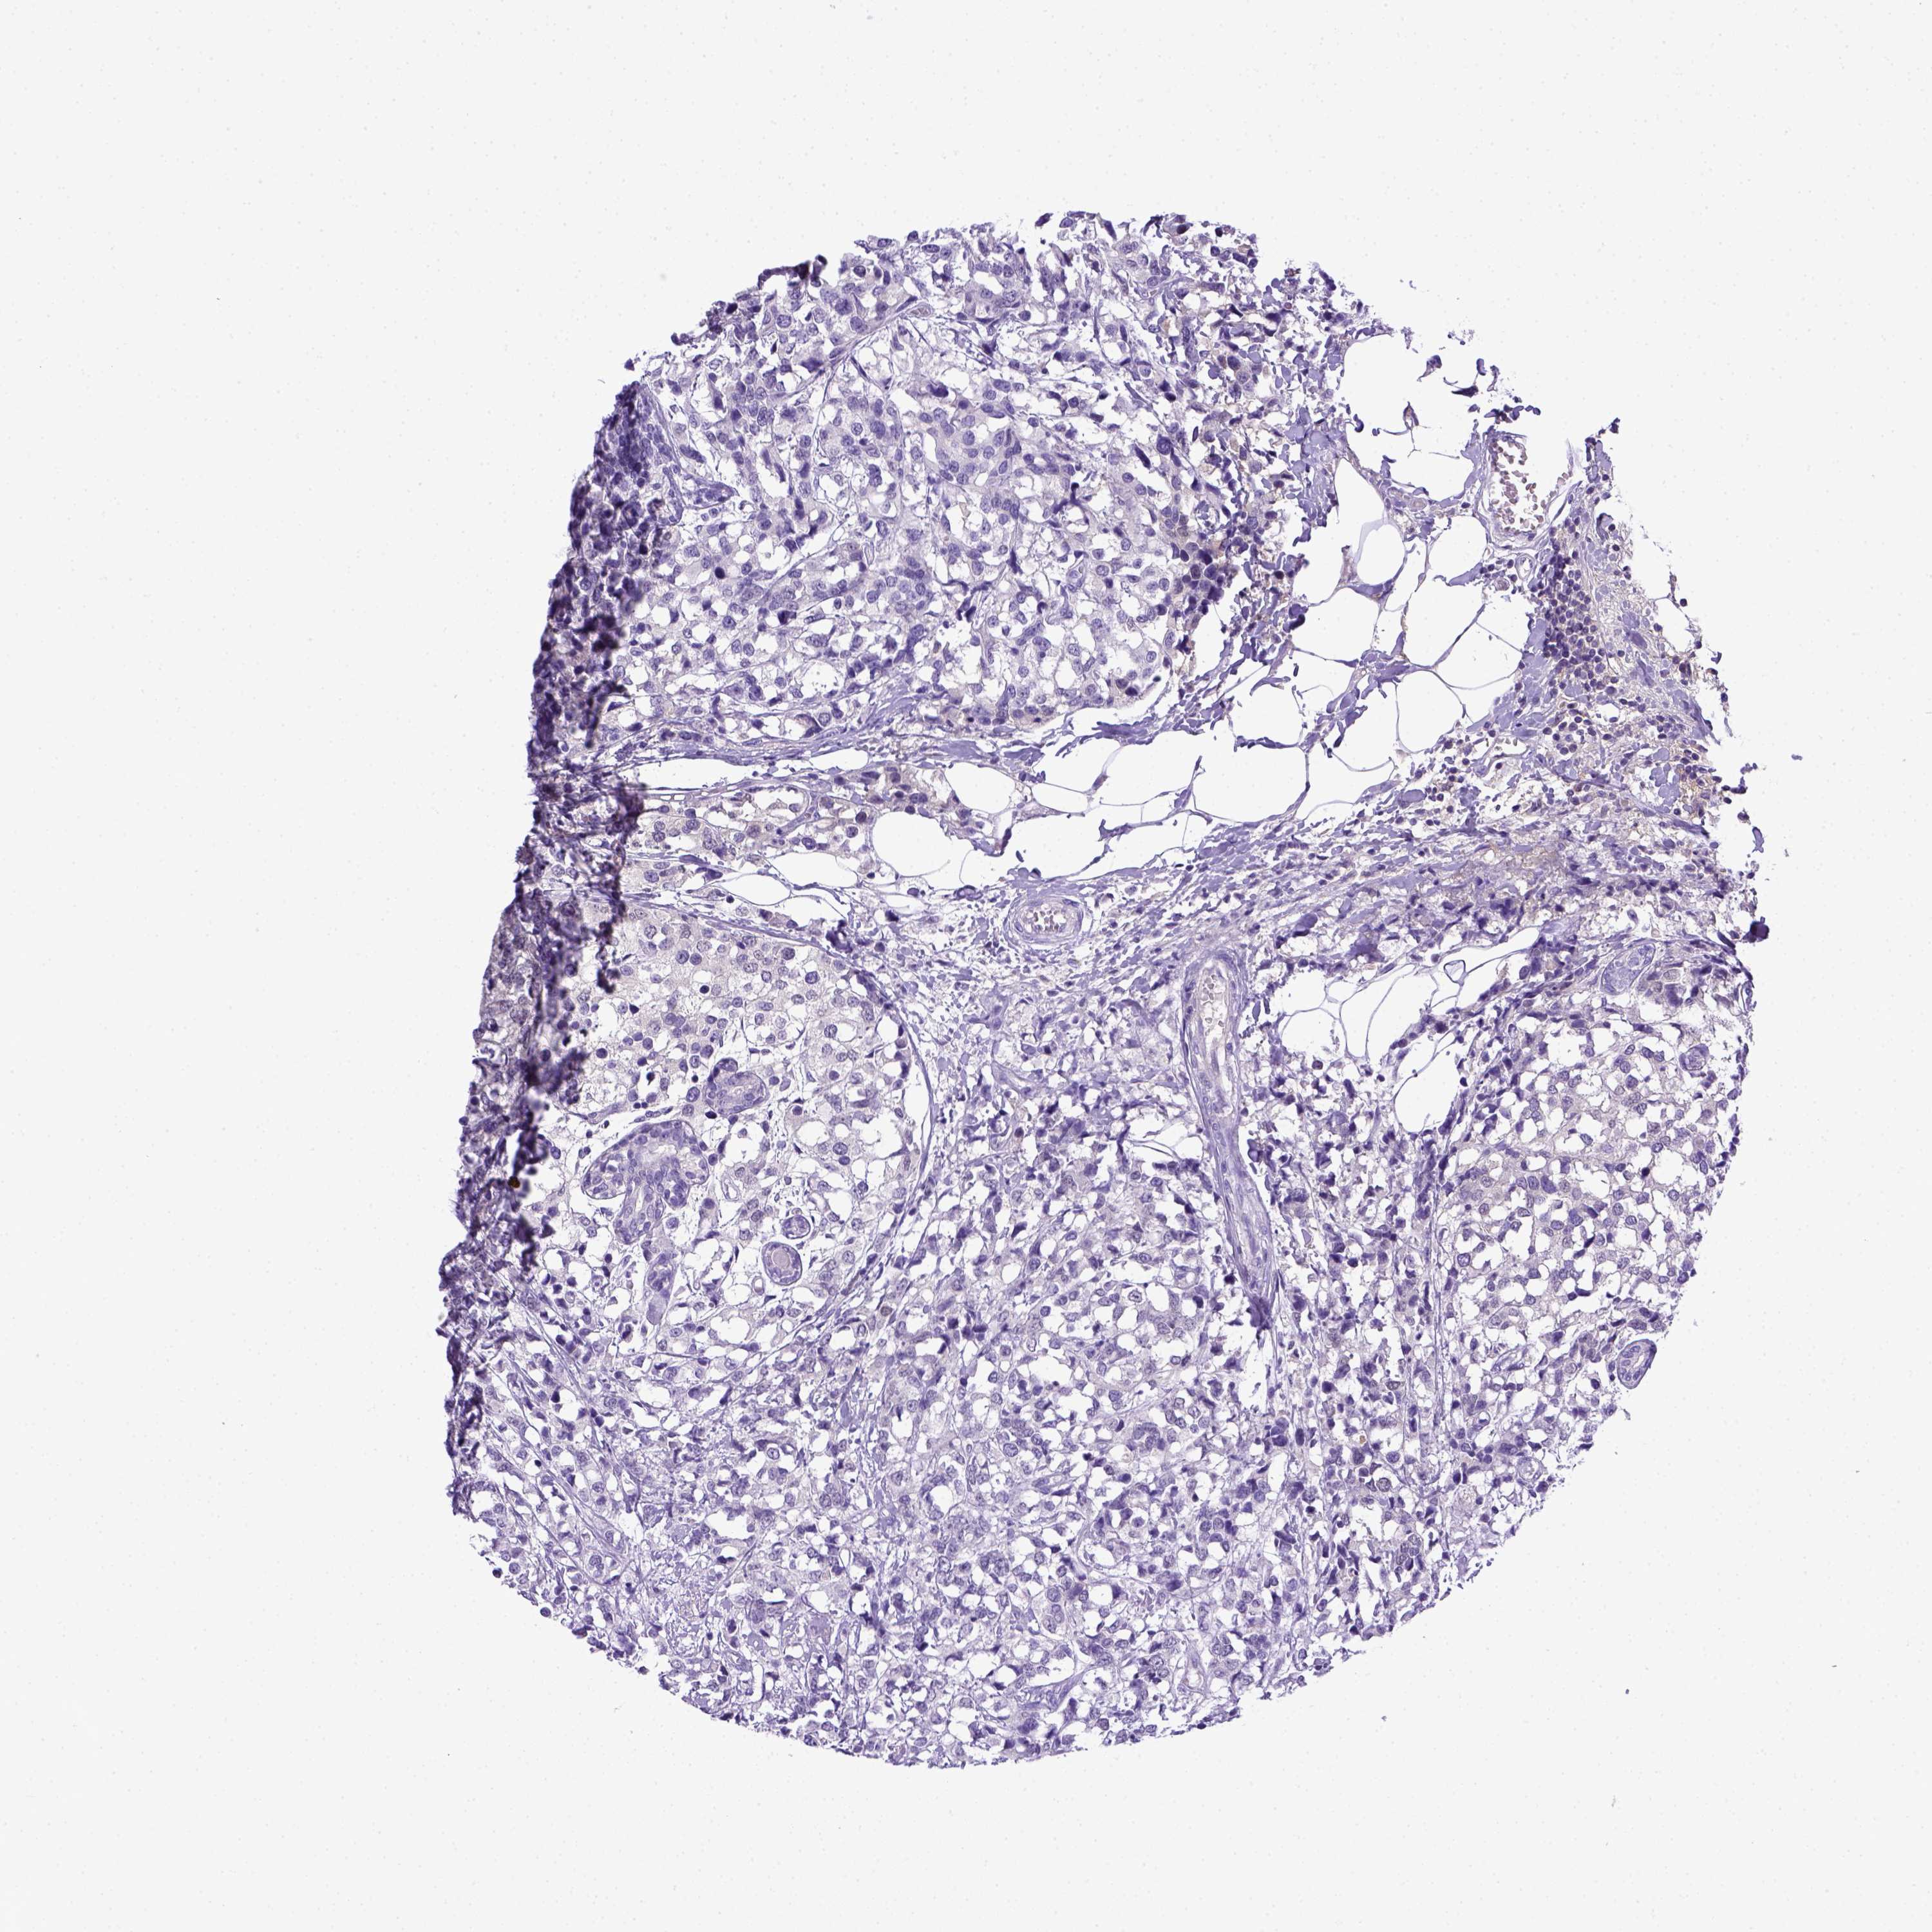

BRCA TCGA BRCA VALIDATION PROTEIN EXPRESSION

ANTIBODIES

AND

VALIDATION